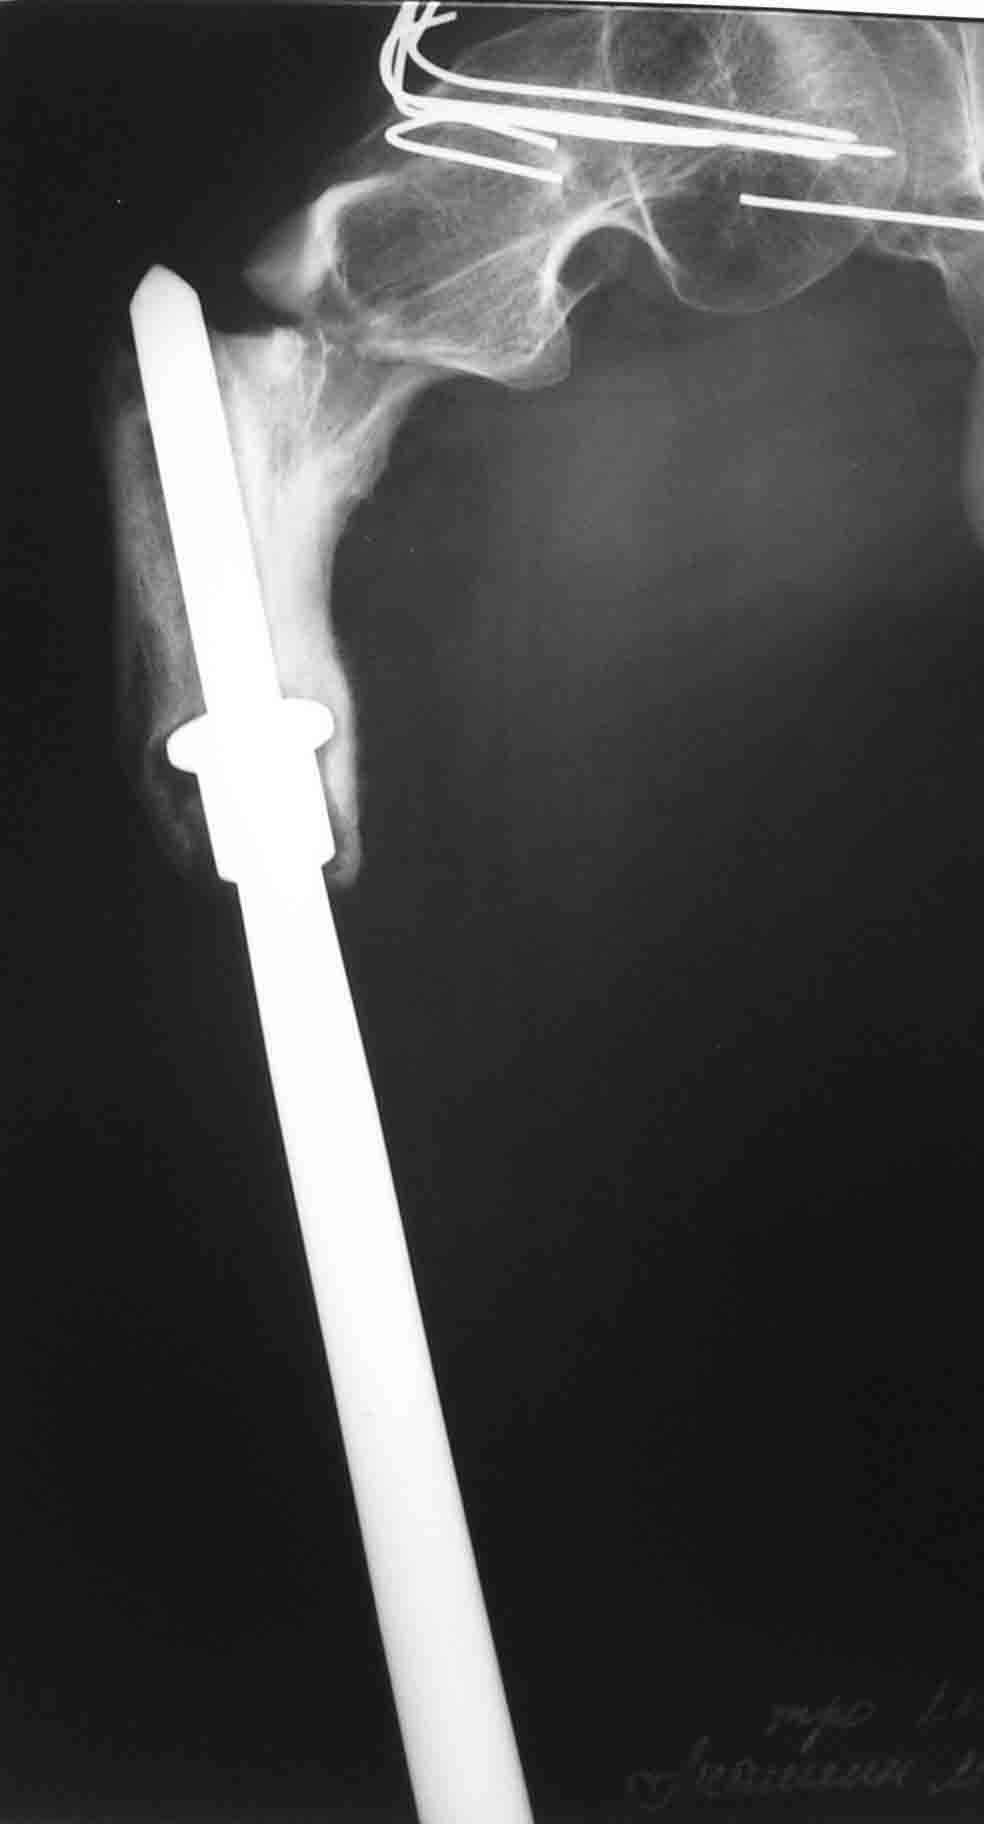

В 1998 году - перелом шейки бедра- оперирован в детской больнице (остеосинтез пучком спиц). В 2001 году- подвертельный перелом (полгода в коксите- сращение). В марте этого года- повторный подвертельный перелом (см RG). В настоящее время в коксите. Что дальше? Облздрав выделяет на лечение чуть более 100 тыс руб. (квота) Может кто-нибудь помочь пациенту? С уважением Ганин Алексей.

In 2001 subtroch fracture, 6 months in plaster casr - healing was reached.

March 2004 - a new fracture at the place, images attached. Now the patient is in the cast again.

"subtotal resection of the femur for osteosarcoma" How much femur was removed or left? It's hard to tell from the radiographs.

I'll request more informative views. But at the presented view of the

proximal femur the bone end can be seen - just below the "collar".

Создается впечатление, что причиной повторного подвертельного перелома бедра является нестабильность протеза( сложно судить о тибиальном компоненте по Рг грамме, но видимая часть бедра - на всем протяжении зона остеосклероза с истончением кортикала) Нестабильное *железо* вызывает резорбцию кости, ее ослабление и как результат -перелом ( обычно на уровне верхушки ножки протеза - зона стресса).